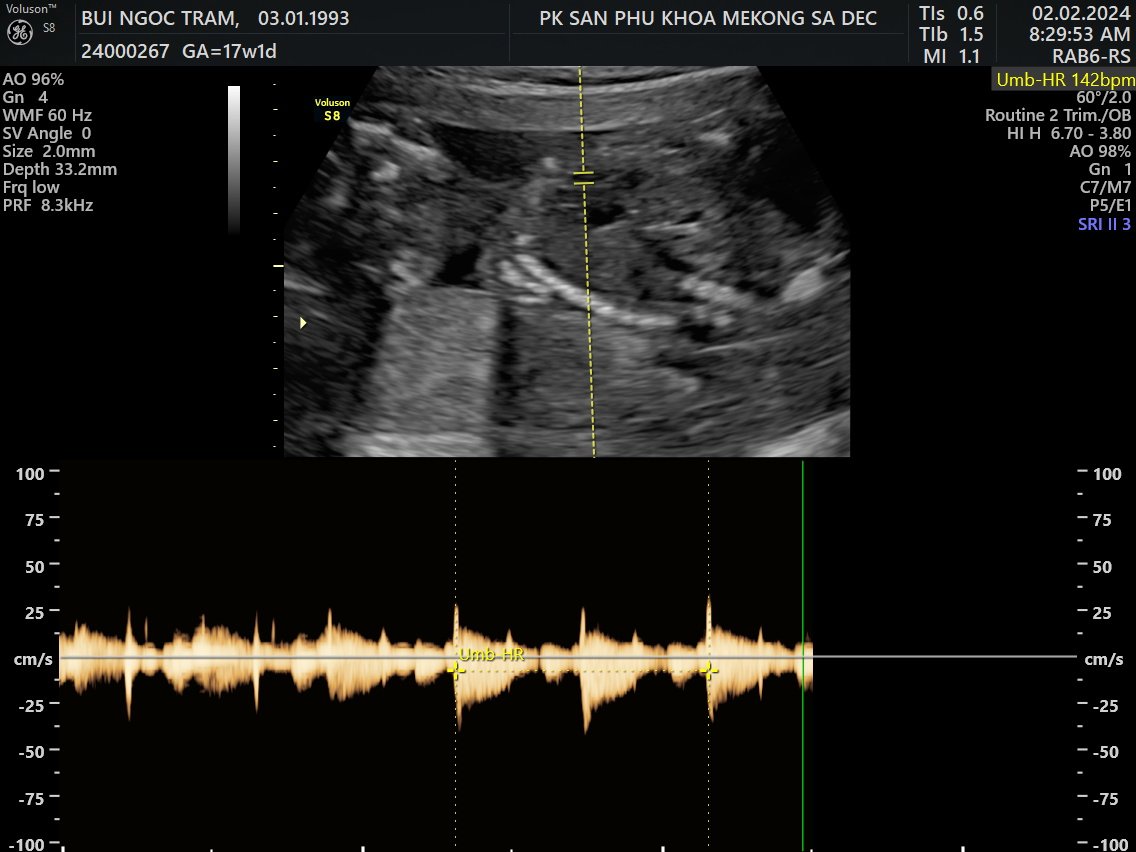

5. Siêu âm 5D

Tuần 17

2 Feb 2024

Về Sadec, được đi siêu âm 5D

Là con trai, hơi ú và hành mẹ bị viêm bạch huyết, hên là phát hiện sớm và được bác sĩ cho thuốc!